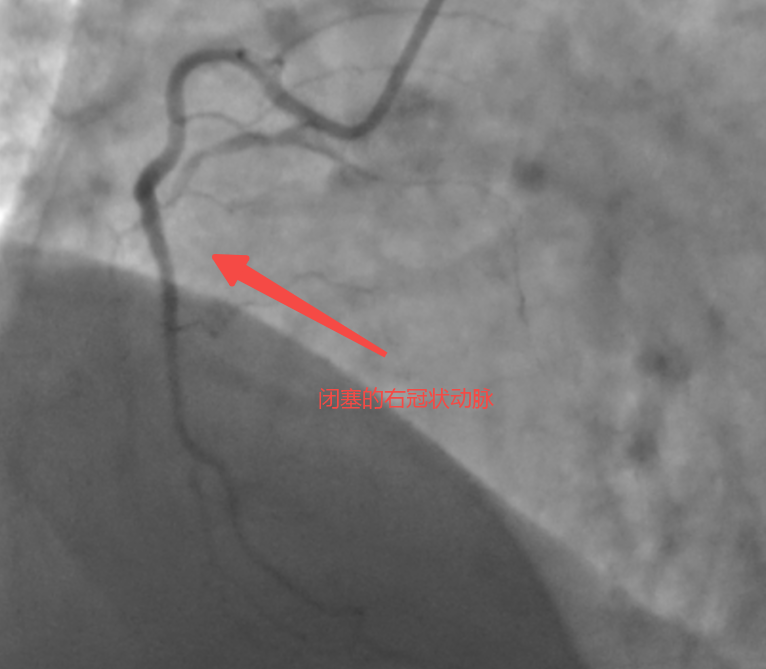

57岁的患者张先生(化名)近1年以来反复出现胸闷症状,经当地医院检查后被诊断为“慢性完全闭塞病变(CTO)”,心脏处三根大血管发生严重病变,其中很重要的一根血管(右冠脉)完全堵死,还长满“硬石头”般的钙化斑块。当地医院反复尝试介入治疗,均未成功打通血管,且评估认为开胸搭桥的效果也不理想。不愿意接受开胸手术的张先生,慕名来到泰康同济(武汉)医院心血管内科就诊。

慢性完全闭塞病变常被称为“冠脉介入的最后堡垒”,尤其是当血管100%闭塞且伴有严重钙化、迂曲时,正向开通的成功率极低。面对张先生复杂的病情,马志强主任团队经过缜密评估,决定采用国际前沿的“逆向介入技术”,通过心脏内极其细小的侧支循环血管建立通道,从闭塞血管的远端进行逆向开通,犹如在“心脏禁区”中开辟一条生命之路。

术中,马志强主任团队启用三维冠脉造影精准定位侧支路径,以头发丝般纤细的导丝,在侧支血管中实现“毫米级”推进,成功建立逆向通路。随后通过多项正向、逆向技术成功打通血管并植入药物支架,恢复右冠脉血流。术后患者胸闷症状缓解,次日即可下床活动,目前已顺利出院。